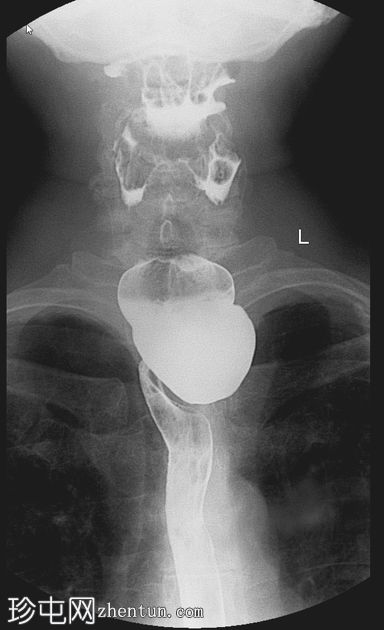

钡餐检查

4.jpeg

正位

可见一充满造影剂的、向后突出的憩室,位于咽食管交界处后壁,大致在T1椎体水平。憩室颈部狭窄,与颈段食管相通。吞咽时憩室充满造影剂,延迟显像显示造影剂滞留。食管其余部分管径和走行正常。未见远端梗阻。

表现为后正中线向外突出的囊状物,颈部狭窄,位于 T1(C5-C6)水平或略低于该水平。

钡餐侧位片显示最佳。